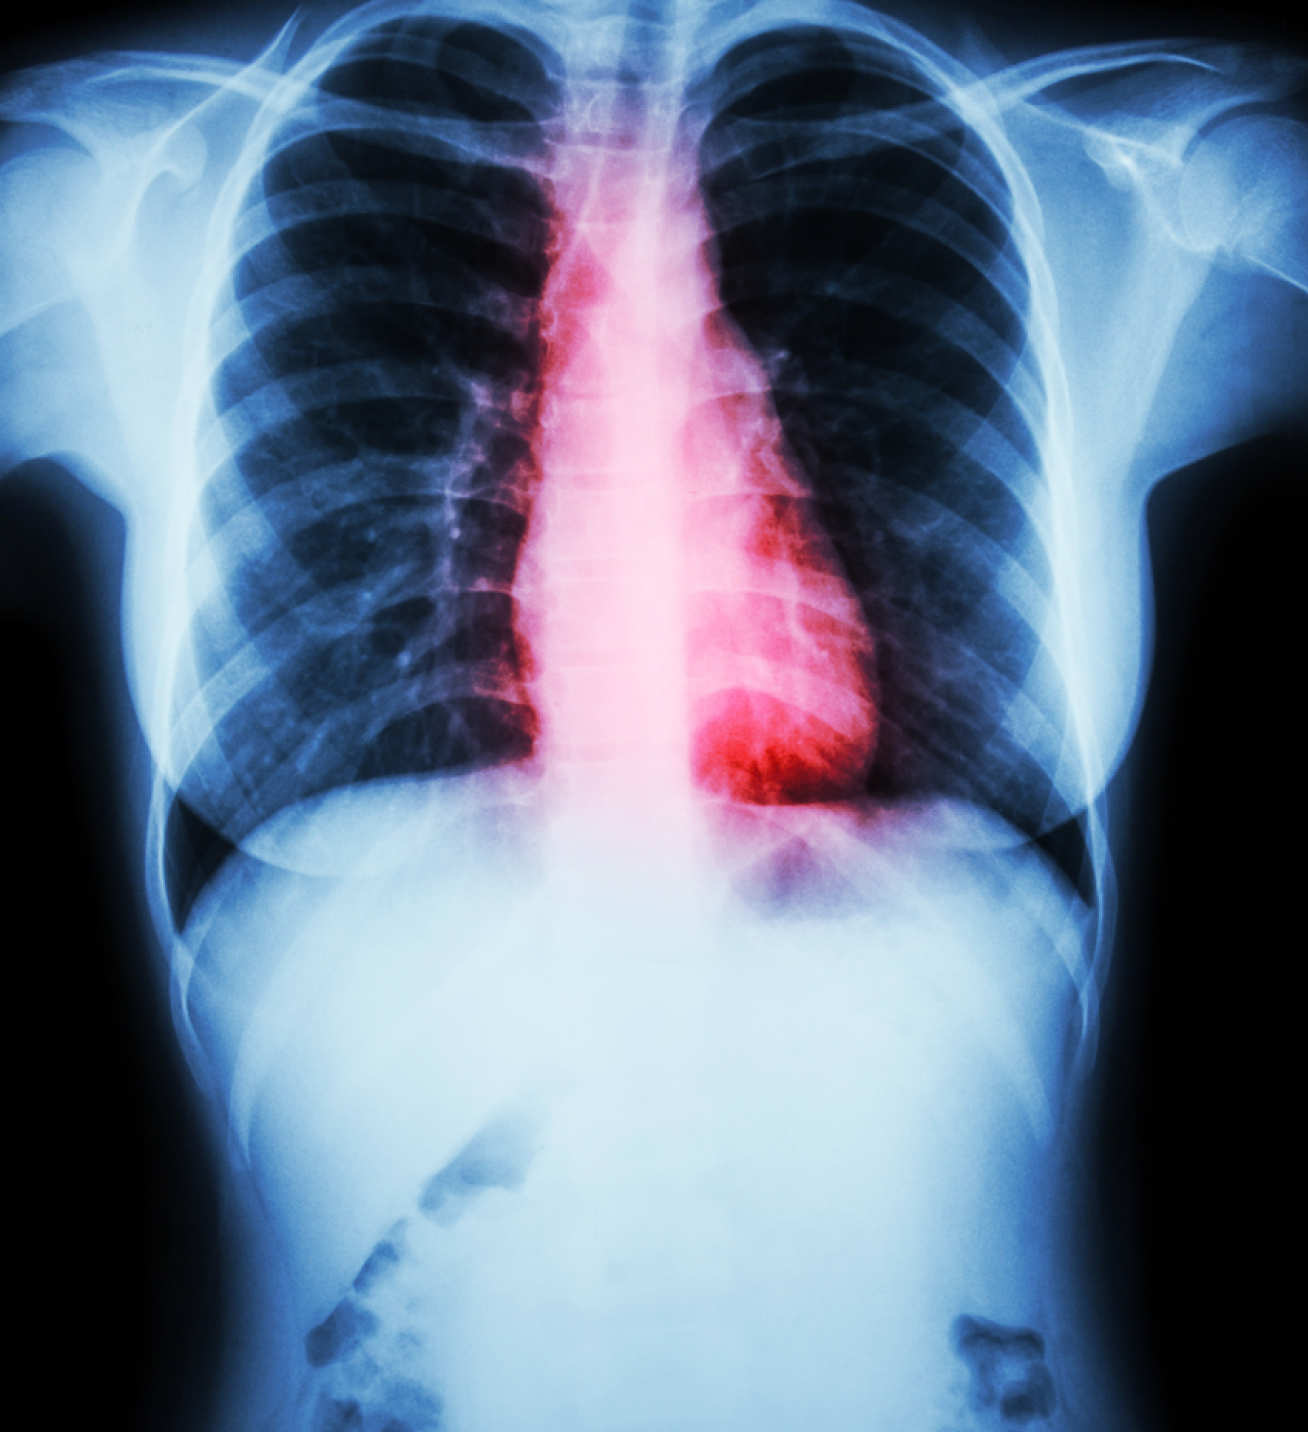

Salt intake has been linked to an increase in cardiovascular disease – including heart attacks and stroke – as well as to an increased risk of stomach cancers. Adults are advised to eat no more than 6g (one teaspoon) a day, or 3g a day for children.  However, adults in England are thought to eat an average of 8g a day and two in three people consume too much salt – with most of this coming from processed foods such as bread, processed meats and ready meals.